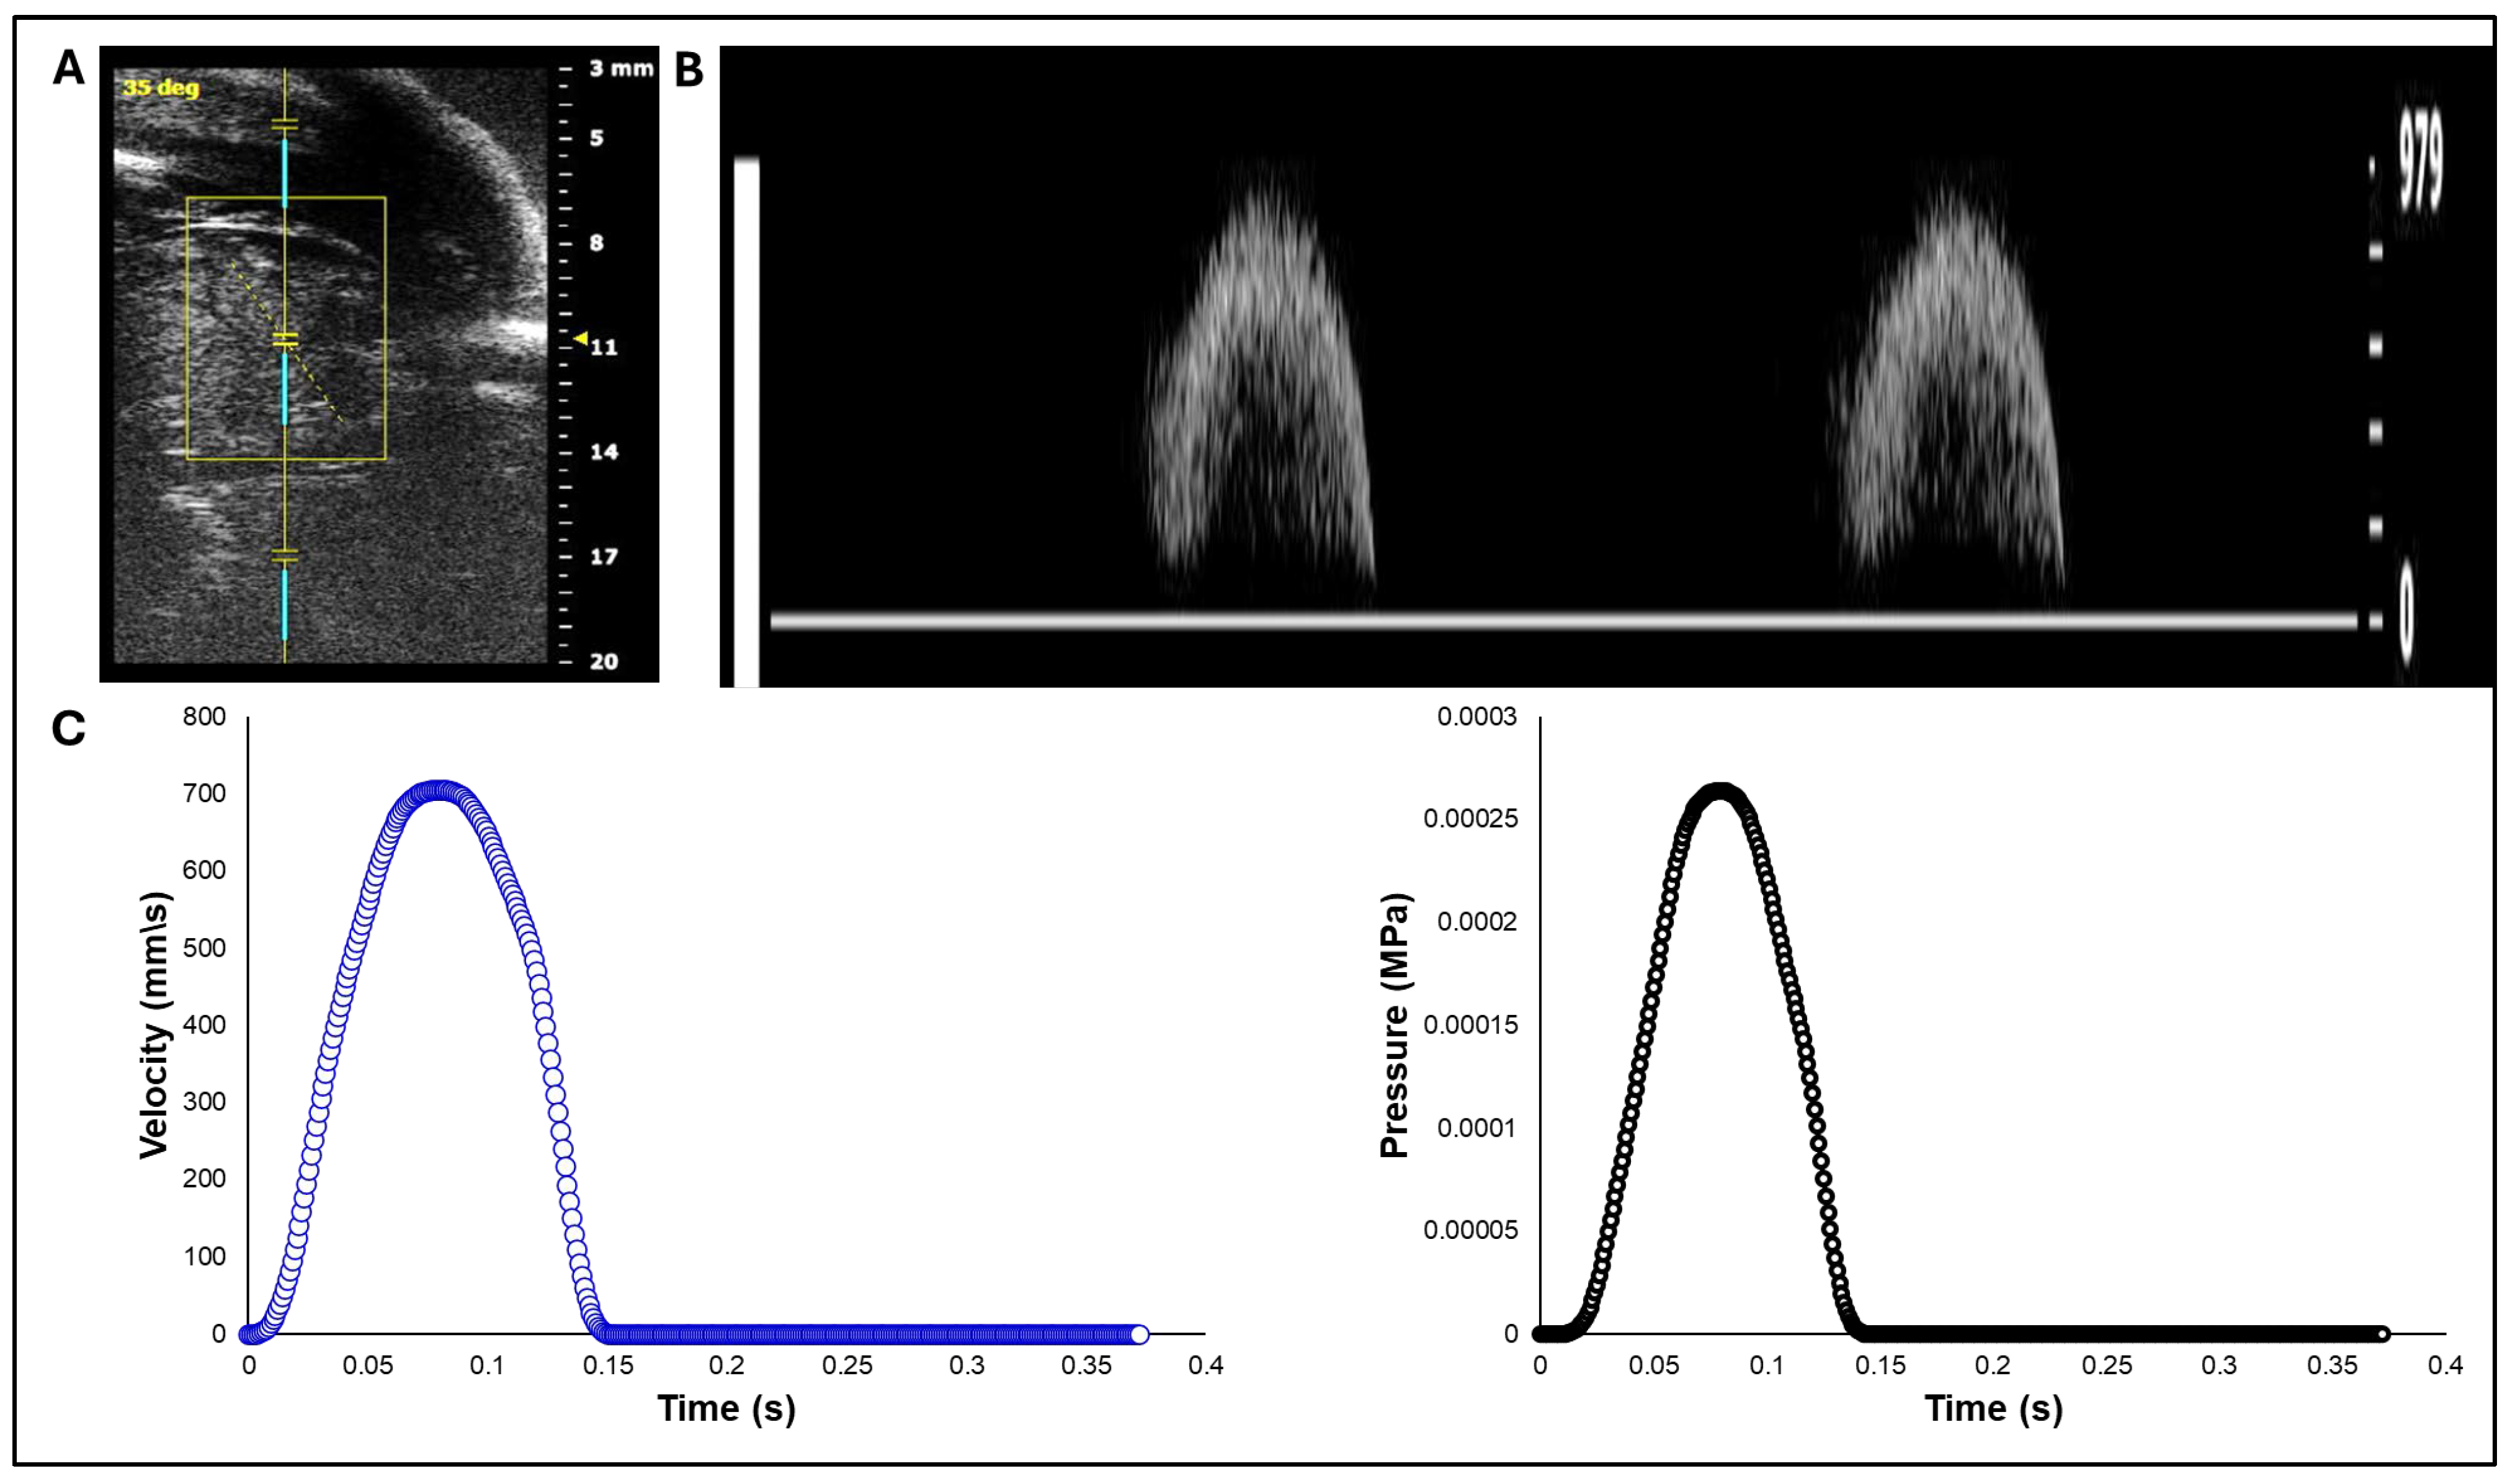

White leghorn chicken eggs were incubated for about 14 days to the Hamburger-Hamilton [33] avian developmental stage 40 (HH40). Chick embryos were imaged in ovo by creating a small window in the eggshell to expose the chorioallantoic membrane and underlying cardiovascular structures. In vivo imaging was performed with high-resolution ultrasound using the Vevo 2100 system (VisualSonics, Fujifilm) equipped with an MS550S-0018 transducer (center frequency: 40 MHz, axial resolution: ~40 µm). Long-axis B-mode images of the left ventricle and ascending aorta were acquired to guide Doppler measurement. Pulsed wave (PW) Doppler mode was used to assess blood flow velocity. The Doppler sample volume (gate) was positioned distal to the valve to capture the systolic outflow velocities. The insonation angle was maintained below 60° to minimize angular error in velocity estimation (Figure 1A). Recorded velocity-time waveforms (Figure 1B) were converted to pressure-time profiles using Bernoulli’s equation to apply as a load boundary condition in FEA (Figure 1C).

Figure 1. Doppler ultrasound–based acquisition and processing of aortic velocity over the cardiac cycle from HH40 (Day 14) chick embryo. A) Imaging setup and location of the Doppler sample volume (gate) positioned distal to the aortic valve, with an insonation angle of about 35 degrees. B) Pulsed-wave Doppler velocity waveform. C) Aortic blood flow velocity from a single cardiac cycle extracted from the Doppler waveform (left) and its corresponding pressure-time profile obtained using the simplified Bernoulli equation (right), used as a load boundary condition in FEA.